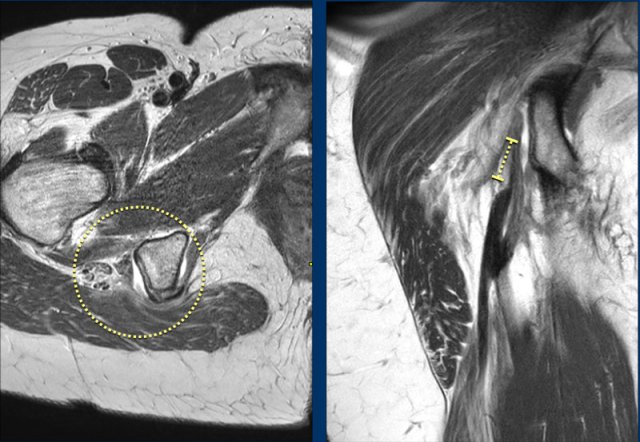

Ischiadic nerve involvement

This image shows a partial injury of the conjoined tendon of the right leg (yellow circle).

There is a large amount of surrounding hematoma in the muscle and alongside the fascia.

The edema surrounds the ischiadic nerve (yellow arrow), which can lead to neuropathy.

However there is a poor correlation between the MRI findings and the symptoms of the patient.

In this case, the partial injury is less pronounced. Still, the ischiadic nerve is enlarged and flattened due to the injury edema.

All features of possible nerve involvement (nerve enlargement, flattening, nerve edema, surrounding edema or surrounding fibrosis) are noted.

Old injury

After the injury, it is possible that the tendon looks normal after healing. However, in most partial injuries, fibrous scarring is seen at the site of the previous injury (yellow dotted circle).

Quite often, when MRI is made for an acute injury, other sites of fibrous scarring of older injuries are seen.